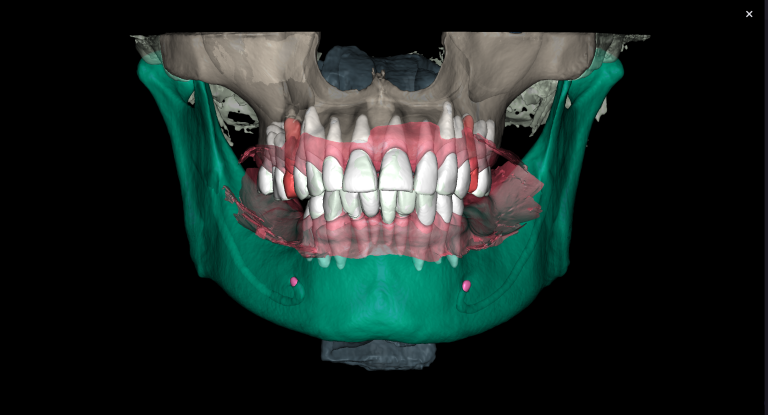

In order to predict the prognosis of the tooth, data from the Diagnocat radiological report and visualization capabilities of the 3D-Viewer tool were utilized, in addition to a clinical examination

Virtual models of the template for guided implant surgery can be created using the “STL” module of Diagnocat. To do this, intraoral scan data is loaded into the module, and a suitable CBCT is selected for merging

Collaborating with Diagnocat AI in treatment planning can increase the quality and accuracy of the procedure, ensuring the long-term success of dental implant surgery